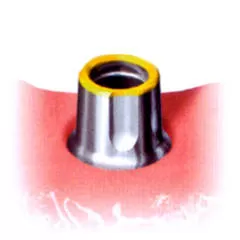

- Абатмент